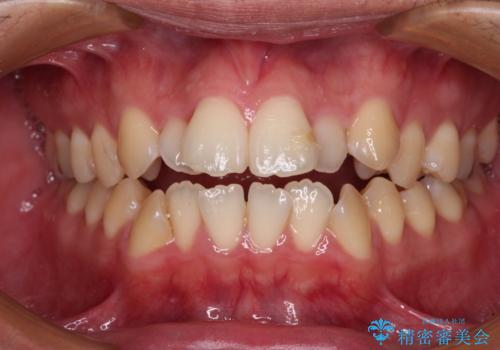

開咬とデコボコを整える インビザライン矯正治療

- 前歯の開咬と叢生を気にして来院された患者様です。

開咬の治療は、前歯を閉じるように動かすとともに、上下臼歯を圧下(骨内にめり込ませる)させることで進めて行きます。

インビザラインは臼歯の圧下を効果的に行えるため、インビザラインを用いて矯正治療を行うこととしました。また、アンカースクリューを用いて、口元の突出感の改善を図りました。